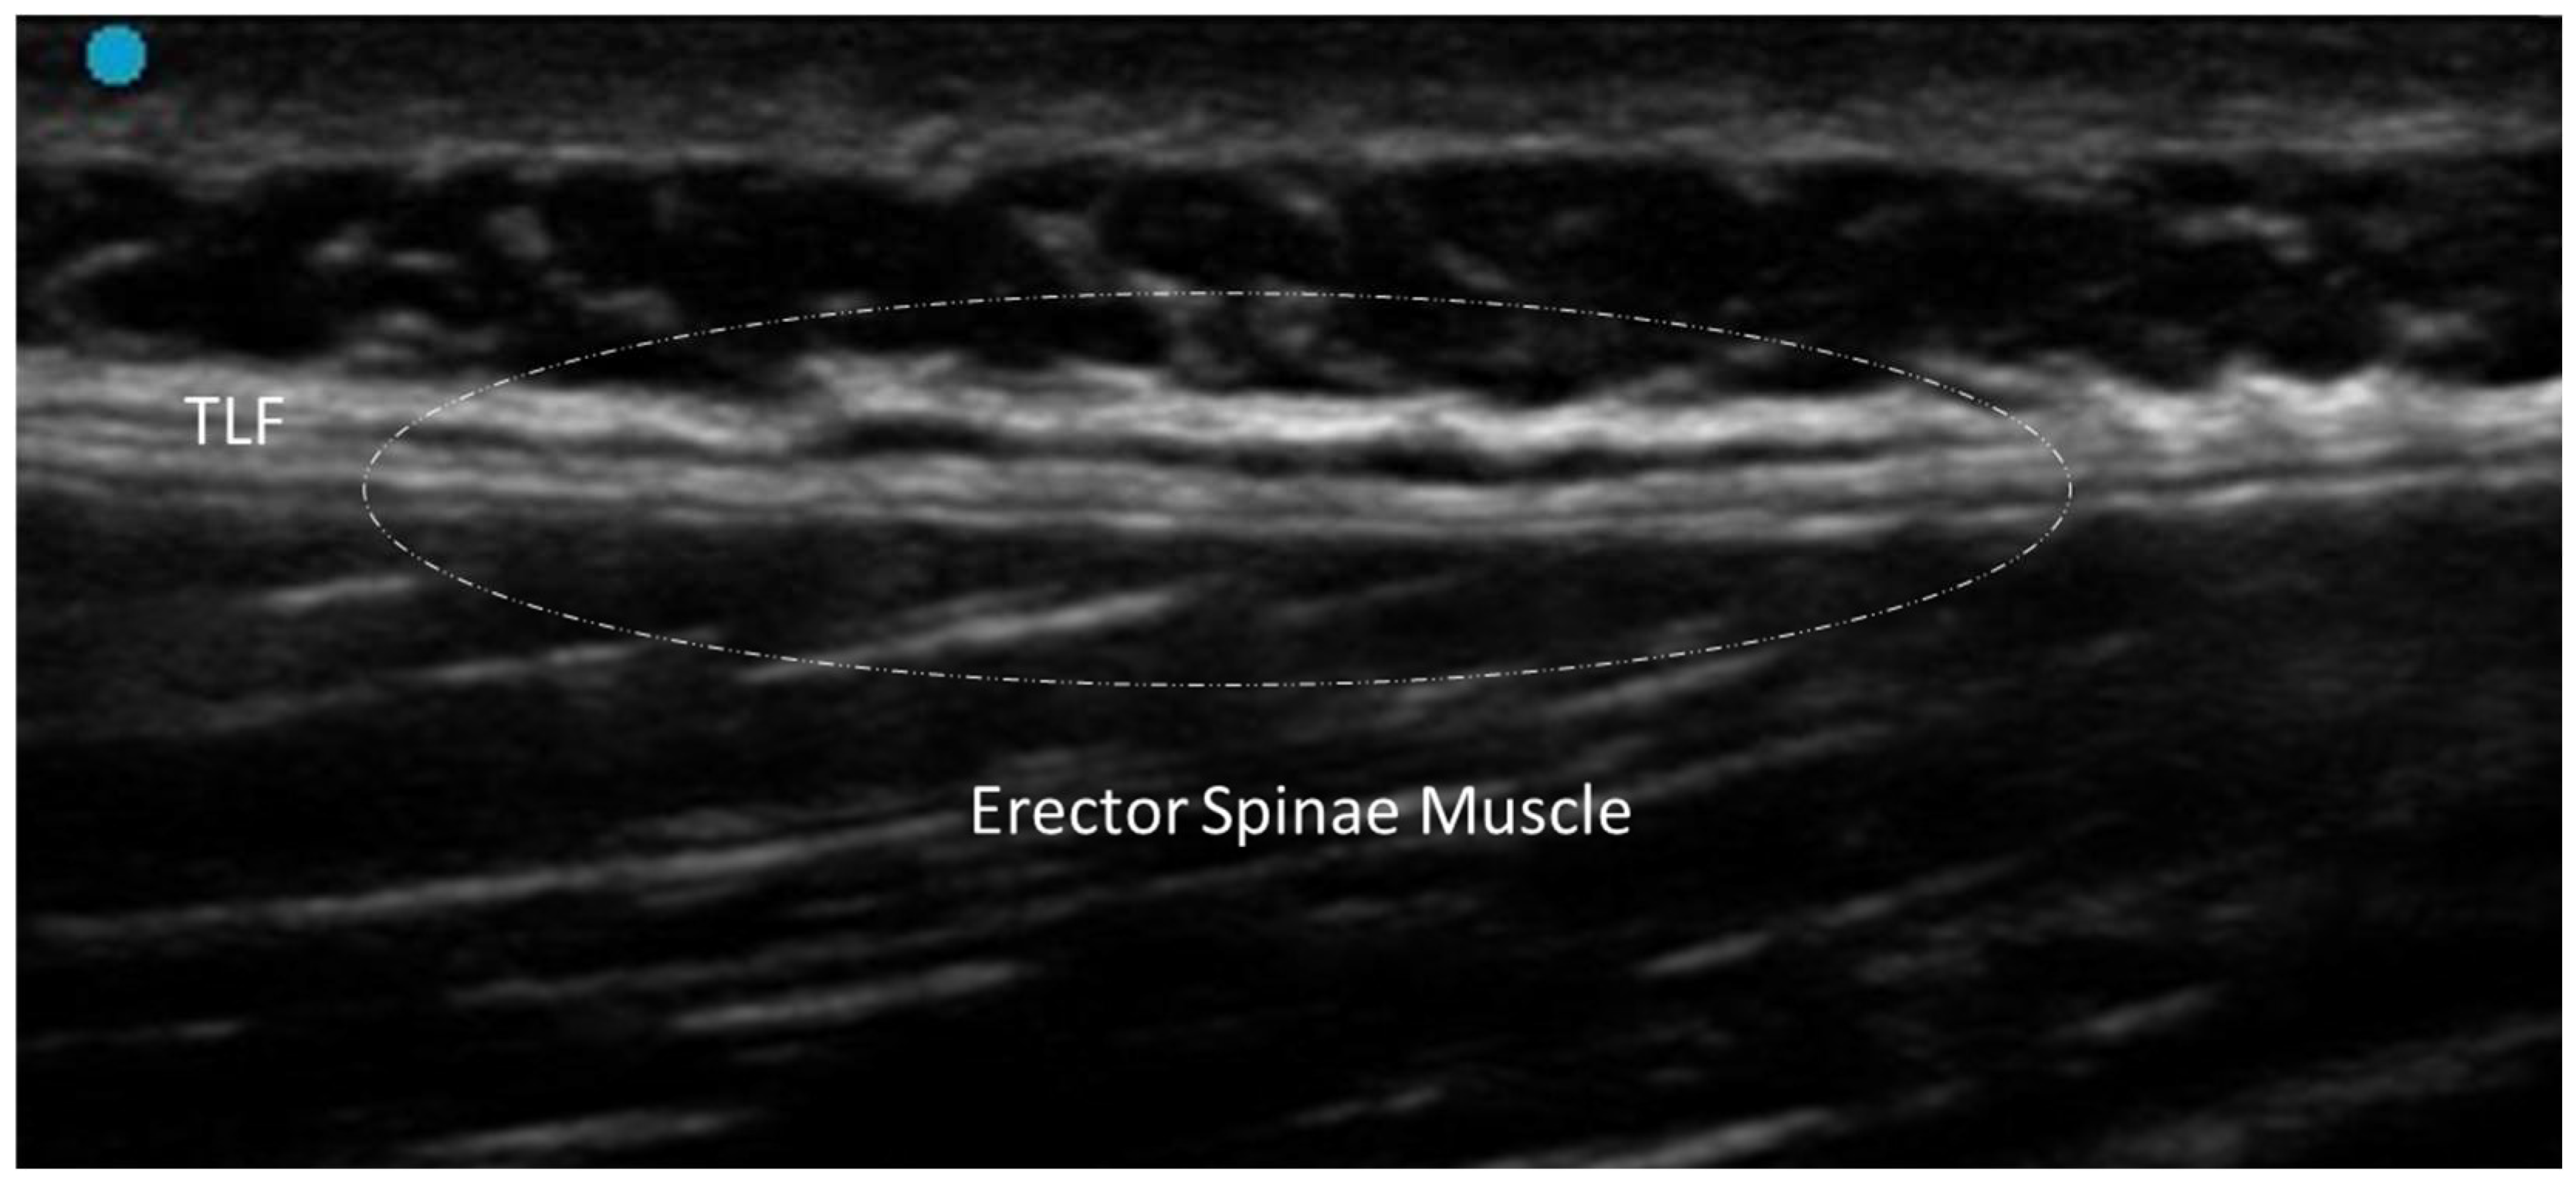

3.5.3. Myofascial Trigger Points